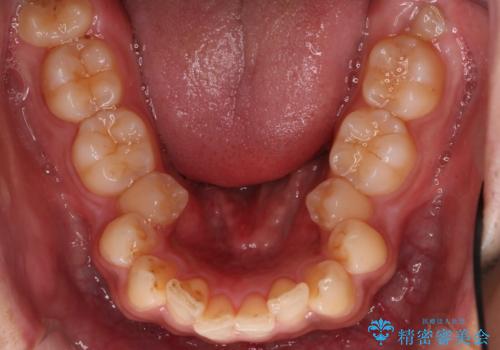

【審美ワイヤー】奥歯のガタガタを治したい

- 歯並びの凸凹を主訴に来院されました。

スペースが必要なため、抜歯を行なって治療を行いました。

奥歯の捻れが強く治療期間がかかりましたが、綺麗な仕上がりに満足していただきました。